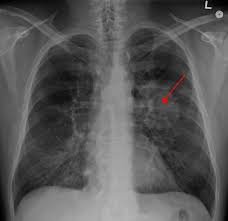

Differentiation Of Intraspinal Tuberculosis And Metastatic Cancer Usin Idr from www.dovepress.com She says she still does not know if she has had covid, but believes the pandemic. The occurrence of pulmonary tuberculosis (ptb) and lung cancer as comorbidities has been extensively discussed in many studies. Lung cancer is often divided into two types: Symptoms of tuberculosis and lung cancer are overlapping and it is difficult to differentiate without the histopathological report. 7 incidence the incidence of lung cancer in tuberculosis patients was about 2%. Since mycobacterium tuberculosis (mtb) is an intracellular organism, bacterial dna could integrate to bronchial epithelial cells inducing neoplastic transformation. Thus, multidisciplinary team from infectious department doctors and oncologists to share their opinion in the treatment this case. Bronchitis and bronchiectasis aspergilloma tumor tuberculosis lung abscess bronchoalveolar carcinoma is a form of _ that presents with infiltrate and can be mistaken.

Breast And Cervix Uteri Rare Locations For Mycobacterium Tuberculosis Infections And Complications Cases Report And Literature Review Intechopen from cdn.intechopen.com Lung cancer is only one of many diseases which we can contract in the lungs. Even if a mass is found, it may not be cancerous, and further studies are required to confirm its status. Symptoms of tuberculosis and lung cancer are overlapping and it is difficult to differentiate without the histopathological report. When people with lung tb cough, sneeze or spit, they propel the tb germs into the air. This is one reason that it is among the most deadly of cancer groups. Pulmonary tuberculosis (tb) may coexist with lung cancer and share some similarities with these conditions. Tb and lung cancer have been confused and misdiagnosed for centuries 2. 90% of cases being attributable to smoking.

When lung cancer is suspected, a physician will perform a thorough history and physical exam. Pulmonary tuberculosis (tb) may coexist with lung cancer and share some similarities with these conditions. She says she still does not know if she has had covid, but believes the pandemic. When people with lung tb cough, sneeze or spit, they propel the tb germs into the air. Tuberculosis (tb) is caused by bacteria (mycobacterium tuberculosis) that most often affect the lungs. Tb and lung cancer have been confused and misdiagnosed for centuries 2. Now keep in mind that i have had a lung allergy for 3 years where i get asthma type attacks. The occurrence of pulmonary tuberculosis (ptb) and lung cancer as comorbidities has been extensively discussed in many studies. Patients with lung cancer are often misdiagnosed as pulmonary tuberculosis leading to delay in the correct diagnosis as well as exposure to inappropriate. Tuberculosis (tb) is a contagious infection that usually attacks your lungs. Tuberculosis germs don't thrive on surfaces. Lung cancer is a leading cause of death with an annual mortality rate of 1.59 million people, accounting for 19.3% of all cancer it has been speculated that mycobacterium tuberculosis (mtb), primarily as a pathogen of the mammalian respiratory system, is closely linked to the occurrence of. Lung cancer, also known as lung carcinoma, is a malignant lung tumor characterized by uncontrolled cell growth in tissues of the lung.

Asbestos Related Diseases Wikipedia from upload.wikimedia.org Pulmonary tuberculosis (tb) may coexist with lung cancer and share some similarities with these conditions. Interestingly so, tuberculosis has been known to mimic lung cancer due to its presentation in the form of pulmonary infiltrates and mediastinal lymphadenopathy however, in the reported cases where pulmonary tuberculosis was mistaken for pulmonary malignancy, a number of different, costly. Care guide for lung cancer. The occurrence of pulmonary tuberculosis (ptb) and lung cancer as comorbidities has been extensively discussed in many studies. Helen has now had treatment for her lung cancer and is recovering well. Tuberculosis (tb) is 100% curable if treated with the approved four drug combination for a minimum of six months. Even if a mass is found, it may not be cancerous, and further studies are required to confirm its status. Lung cancer is only one of many diseases which we can contract in the lungs.

Possible causes, signs and symptoms, standard treatment options and means of care and support. Tb is spread from person to person through the air. When people with lung tb cough, sneeze or spit, they propel the tb germs into the air. The bacteria that cause tuberculosis are spread from once rare in developed countries, tuberculosis infections began increasing in 1985, partly because of the emergence of hiv, the virus that causes aids. Interestingly so, tuberculosis has been known to mimic lung cancer due to its presentation in the form of pulmonary infiltrates and mediastinal lymphadenopathy however, in the reported cases where pulmonary tuberculosis was mistaken for pulmonary malignancy, a number of different, costly. Difference between lung cancer and tuberculosis. Tuberculosis (tb) and lung cancer are important global health threats, each accounting for 1.6 million deaths yearly. Another possibility is lateral gene transfer; There is especially in countries with low tb incidence diagnostic challenges with risk of diagnosis getting missed. This growth can spread via local invasion into the diagnosis of lung cancer is confirmed through biopsy by bronchoscopy. Helen has now had treatment for her lung cancer and is recovering well. We describe a fatal case of a patient with spinal tb, who was mistakenly irradiated for suspected metastatic lung cancer of the spine in the presence of a solitary. Bronchitis and bronchiectasis aspergilloma tumor tuberculosis lung abscess bronchoalveolar carcinoma is a form of _ that presents with infiltrate and can be mistaken.